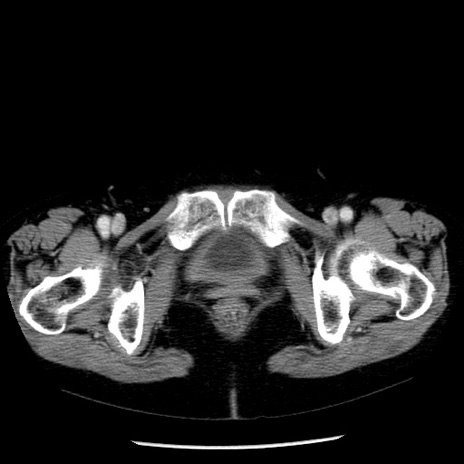

冠状断像